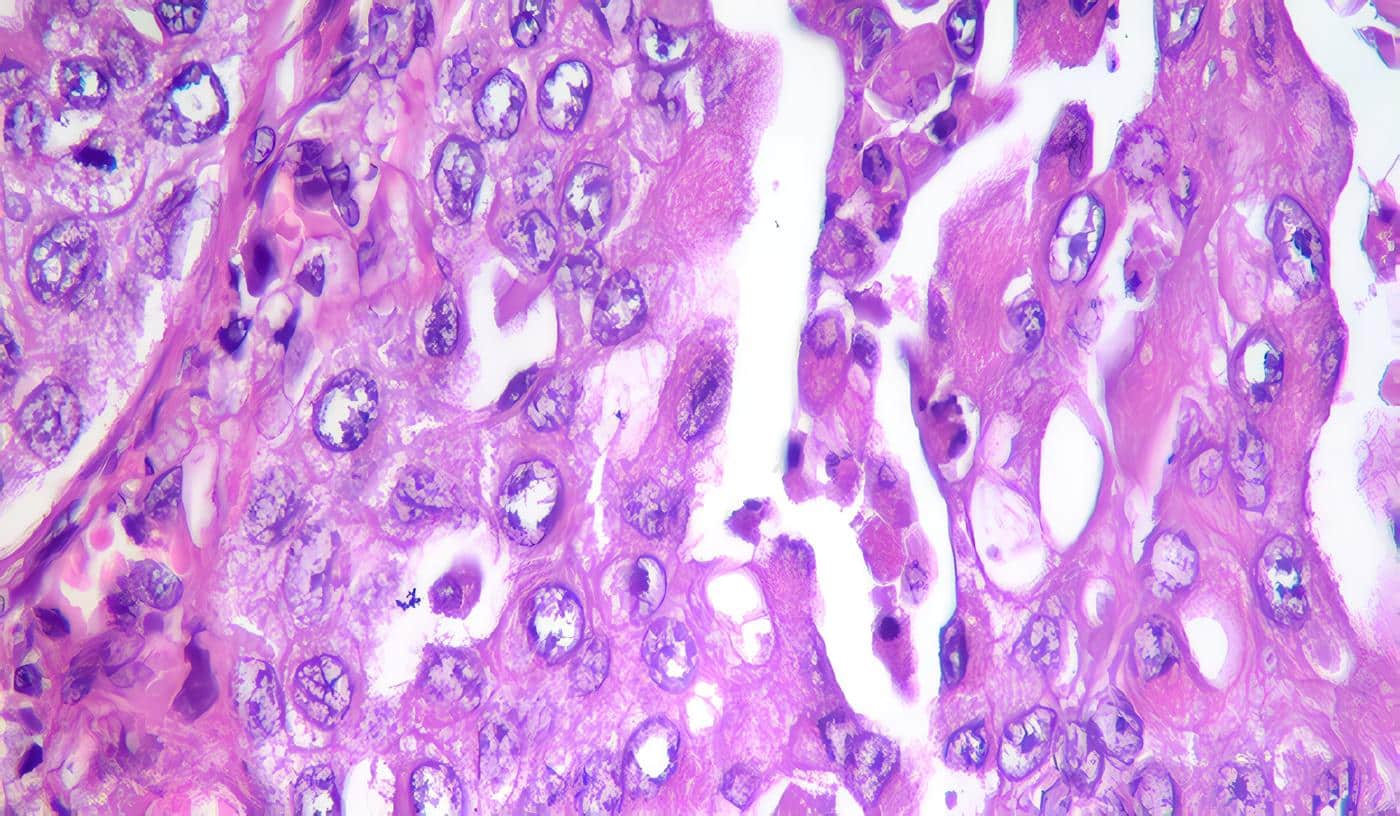

- 38. NEHRA A, GOLDSTEIN I, PABBY A, NUGENTE MATTHEW, et al. Mechanisms of venous leakage: A prospective clinico pathological correlation of corporeal function and structure. J Urol, 1998, Vol 156, 1320-1329.